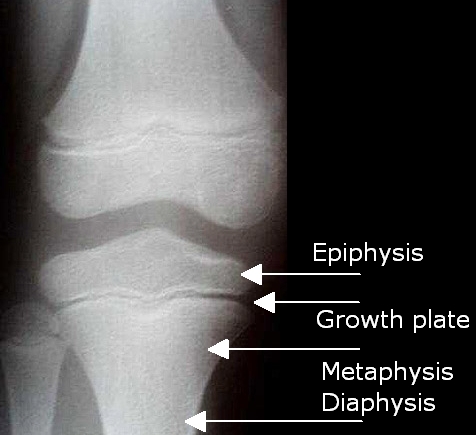

What signals the end of growth and what is Kallmans syndrome?